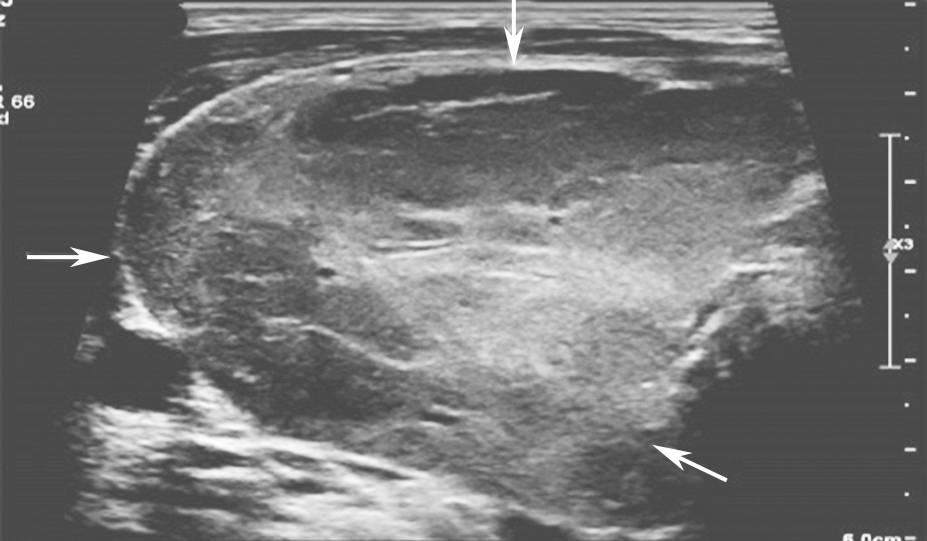

(十二)甲状腺未分化癌

甲状腺未分化癌超声特点为体积较大、边界不清、形态不规则,肿瘤平均长径可达4cm,低回声为主,等回声少见,病变内部常可见液化坏死及粗大钙化,结节内部彩色多普勒血流信号丰富而杂乱(图15),此外,未分化癌局部或者远处转移常见,转移淋巴结内部常伴有液化坏死。

.jpg)

图15颈部正中偏左横切面:甲状腺左叶可见不均匀低回声,形态不规则,边界模糊(箭头所示)